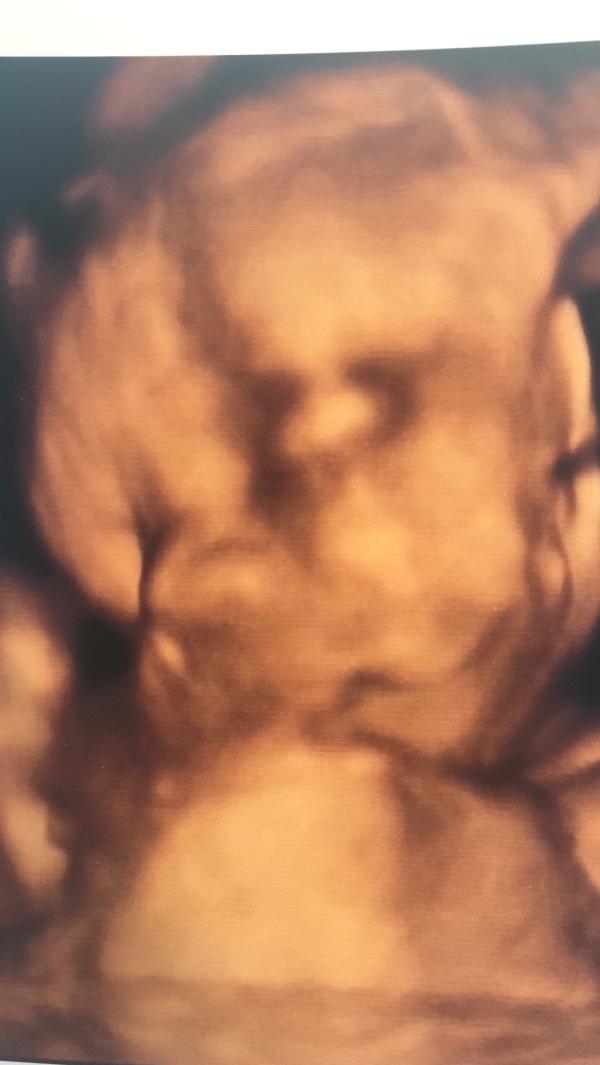

Сходили с мужем сегодня на 3Д УЗИ, очень конечно круто, эмоций море, супруг там чуть скупую мужскую слезу не пустил) врач сказала похож на мужа) главное кровотоки в норме, ИАЖ отличный, развитие по сроку и даже больше , Богатырь 💪🏼💪🏼. Уже почти 1кг весом, такой маленький , а сколько любви. Теперь можно ждать третьего планового УЗИ. Правда мне поставили пиелоэкиазию правой почки, запретили лежать на правом боку, но это такие мелочи, мы справимся ) и наш курносый , любимый ,...